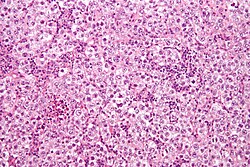

| Germinoma / Seminoma / Dysgerminoma | fried egg cells | fried egg-like cells (central nucleus, clear cytoplasm) with squared-off nuclear membrane, nucleoli, lymphocytic infiltrate, granulomata, syncytiotrophoblastic giant cells[6] |

D2-40 | seminoma = male version of this tumour; dysgerminoma = female version of this tumour | File:Seminoma intermed mag.jpg Seminoma (WC/Nephron) |